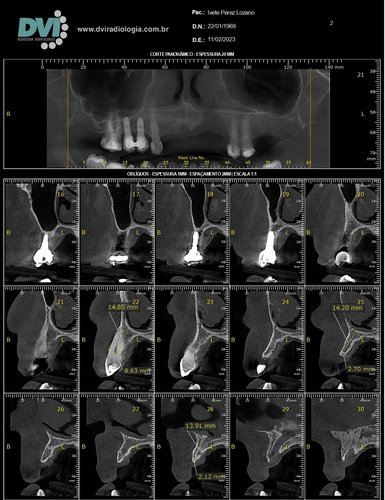

Passamos por vários especialistas e quando chegamos ao dentista da polícia militar, fomos informados que teríamos que fazer uma cirurgia para salvar o dente, cirurgia que durou em torno de 4:00 horas, mas infelizmente não foi possível salvar o dente e junto da perda do dente também tive uma perda óssea.

Tivemos que procurar um dentista para fazer um procedimento para colocar um dente, onde foi feito outro procedimento que usou os dentes das laterais, e sempre tive problema como esse outro que foi feito.

Procurando outro dentista, isso eu já mais velha, tentamos a opção de enxerto ósseo, onde meu organismo rejeitou, partimos para outra opção que eu podia fazer no momento, onde me encontro até hoje. Mas nesses dias perdi mais um dente e o restante amoleceu, e o resultado é a perda deles. Estou agora em desespero pois trabalho com crianças, falo bastante e quero muito realizar o procedimento chamado protocolo para me sentir segura ao falar, isso tem mexido bastante com minha autoestima e também a dificuldade para se alimentar, mas não tenho condição para isso, quero muito pedir a ajuda de todos(as), que sentirem de me ajudar.